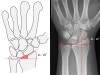

3. Radial inclination

1) The angle between one line connecting the radial styloid tip and the ulnar aspect of the distal radius and a second line perpendicular to the longitudinal axis of the radius.

2) Loss of radial inclination will increase the load across the lunate.